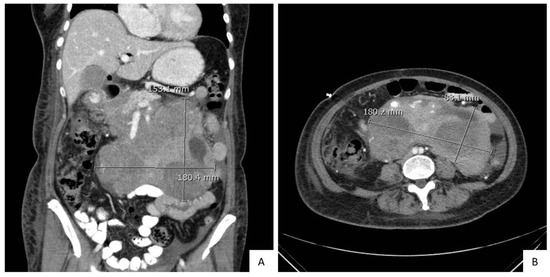

2. Case Presentation